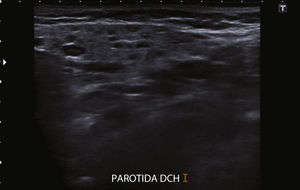

Se trata de una niña de 9 años de edad sana y sin antecedentes personales ni familiares de inmunodeficiencia ni infecciones de repetición. En el último año presenta con frecuencia mensual, episodios de inflamación de ambas parótidas, de 1-2 días de duración, con predominio del dolor durante la masticación, sin asociar fiebre ni otra sintomatología infecciosa. La ecografía cervical es compatible con parotiditis crónica recidivante, ya que muestra múltiples quistes y adenopatías intraparotídeas (figs. 1 y 2).

El diagnóstico de PRJ es fundamentalmente clínico, apoyado en técnicas de imagen. En los últimos años la ecografía5 ha desplazado a la sialografía, ya que muestra una elevada sensibilidad sin necesidad de irradiar al paciente.